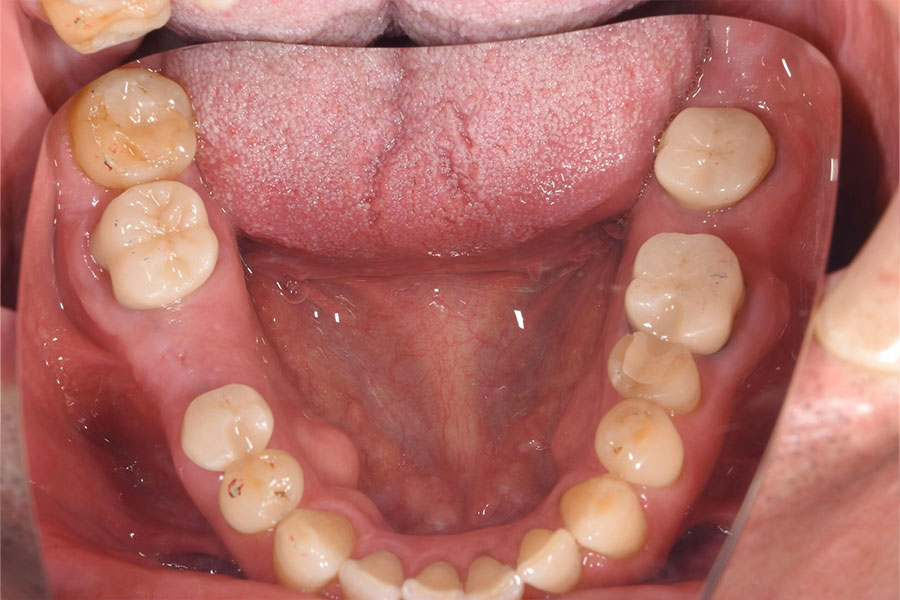

Before -下顎-

After -下顎-

| 施術内容 | 金属アレルギー予防を目的に、金属フリーの自費補綴へ変更。適合性・清掃性・審美性の向上が得られています。 |

|---|---|

| 治療期間 | 約4ヶ月 |

| 費用 | オールセラミックインレー 693,000円 |

| リスク・副作用 | 治療にともない、歯の破折や歯質の削合、場合によっては抜歯が必要となることがあります。また、金属や補綴物を除去する際に、完全に除去できない場合もあります。 |